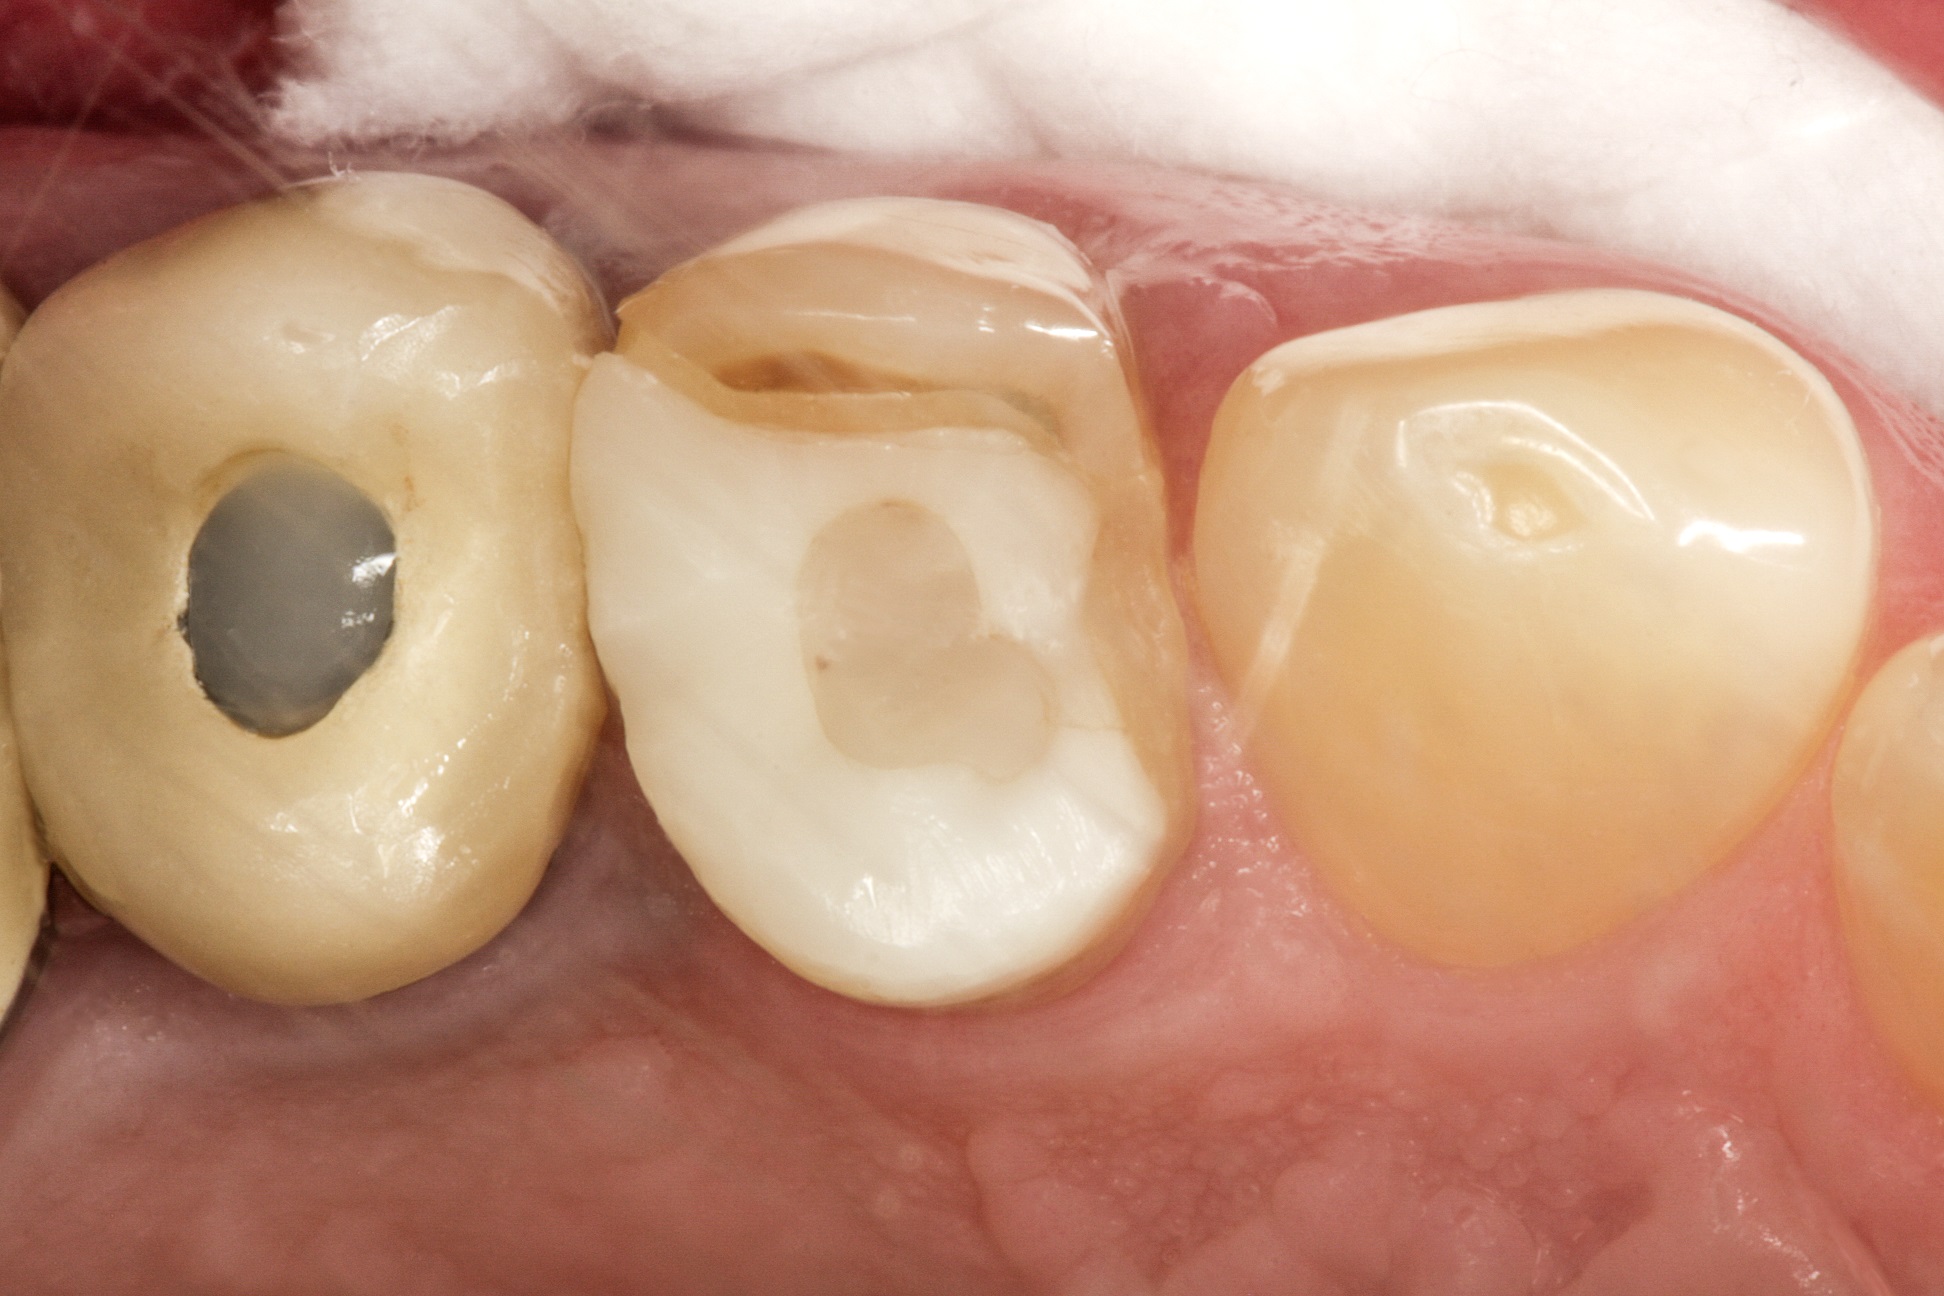

45-річний чоловік звернувся зі скаргою на зуб 24, який

раніше був відновлений за допомогою суцільнокерамічної накладки.

За кілька років після установки накладки знадобилося

ендодонтичне лікування зуба. Тепер було порушено крайове прилягання накладки,

на кераміці видно відколи (рис. 1).

Фото 1. Зуб зі суцільнокерамічною

накладкою.